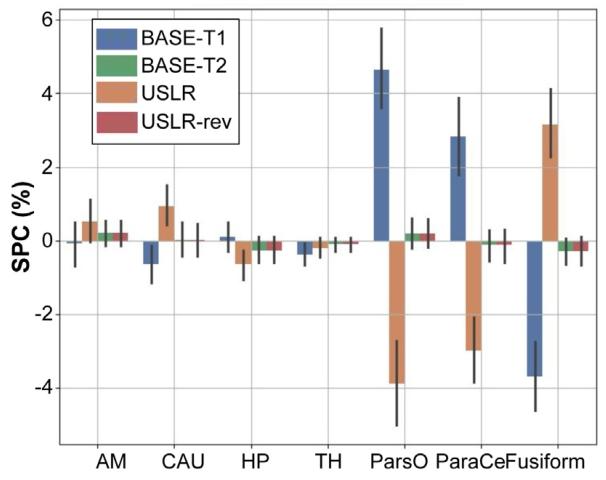

Fig. 2. Symmetrised percent change (SPC) for different cortical and subcorticalbrain regions: amygdala (AM); caudate (CAU); hippocampus (HP); thalamus (TH);pars opercularis (ParsO); paracentral (ParaCe); and fusiform. BASE-T1 (T2) initialisetimepoint 2 (1) with the segmentation of timepoint 1 (2). USLR and USLR-rev processtimepoints in reversed order.

图2 不同皮质及皮质下脑区的对称化百分比变化(SPC):杏仁核(AM)、尾状核(CAU)、海马(HP)、丘脑(TH)、岛盖部(ParsO)、中央旁小叶(ParaCe)和梭状回。BASE-T1(T2)以时间点1(2)的分割结果初始化时间点2(1)的分割。USLR和USLR-rev以相反顺序处理时间点。